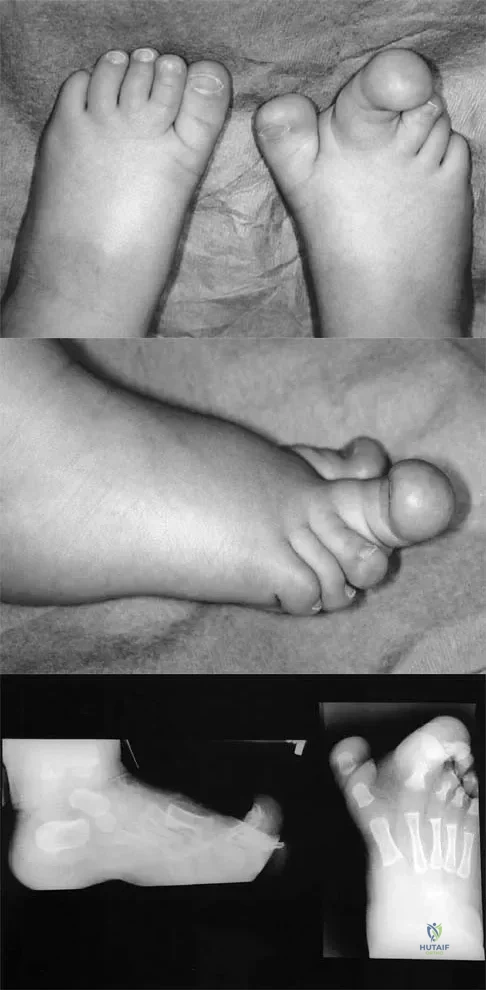

Figures 4a through 4c show the clinical photographs and radiographs of a 12-month-old boy who has progressive difficulty wearing shoes because of the length of the second toe, as well as width of the forefoot. Management should consist of

Explanation